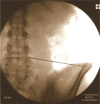

Methods: Six participants with chronic low back pain and lumbar degenerative intervertebral disc (monodiscopathy) disease underwent 1 Platelet-Rich Plasma injection, with a 1-year follow-up. Platelet-Rich Plasma injections were administered into the lumbar intervertebral disc, and outcomes were measured using the Roland Morris Disability Questionnaire, numeric rating scale for pain, Tampa scale for kinesiophobia and lumbar flexion range. Magnetic resonance imaging analysis assessed disc changes.